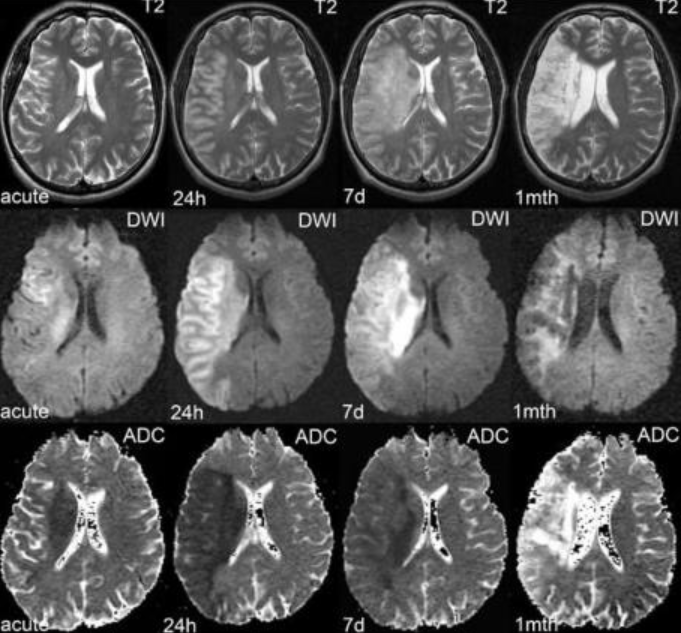

Да, наиболее распространенным методом является КТ, однако роль данного вида диагностики весьма ограничена. Изменения, видимые на КТ, формируются после 24 часов с момента проявлений неврологической симптоматики, на МРТ же с использованием стандартных и специальных методик - в первые минуты/часы (рис. 1).

Рис. 1. Сравнение эволюции визуальной картины ишемического ОНМК в различные временные периоды с помощью программ Т2 и DWI/ADC: чувствительность DWI наиболее значима в первые часы после возникновения инсульта

DWI – диффузионно-взвешенное изображение.  Выявляет инфаркт в первые минуты  с момента сосудистой окклюзии в виде высокого сигнала на DWI с высокими показателями b фактора 800 с/мм2 и сниженного сигнала на ADC-карте. Также зона инсульта определима на Т2-ВИ и FLAIR в виде гиперинтенсивного сигнала, но плохо отличима от аналогичного сигнала зон хронической ишемии,глиоза. Таким образом, программа DWI является ключевой в выявлении ишемического ОНМК.